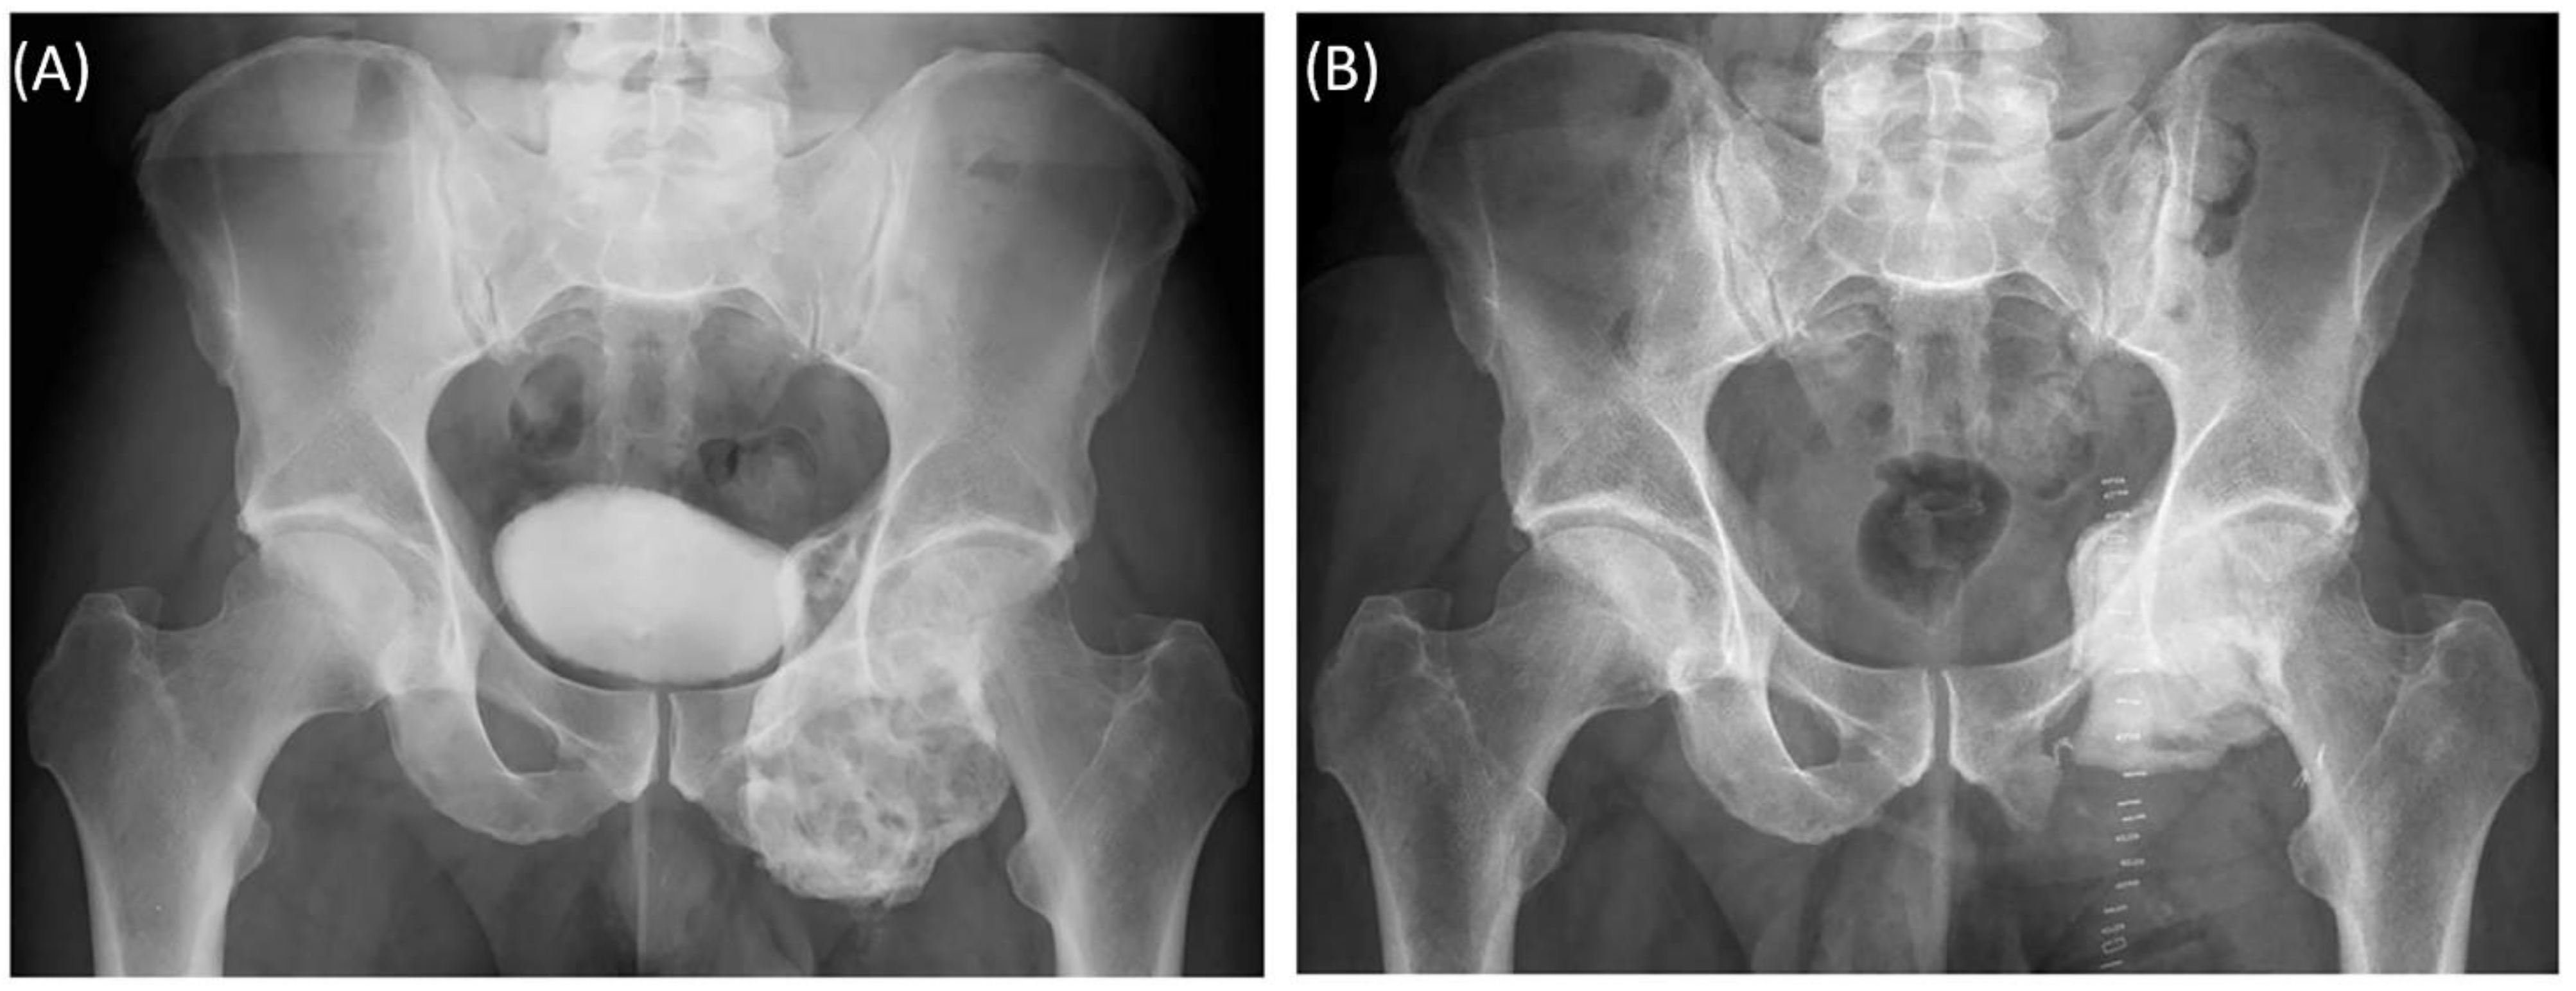

A 58-year-old male patient was diagnosed with a giant cell tumor of the left pelvis in 2013. After five years of conservative treatment with denosumab, he developed recurrent jawbone osteonecrosis. Therefore, the treatment was stopped in 2018. Consequently, tumor progression with increasing symptoms occurred, and surgical resection was indicated after rebiopsy and histopathological confirmation. Intralesional resection was performed via high-speed burr curettage followed by adjuvant polymethyl methacrylate filling (Figure 8 and Figure 9). This approach allowed preservation of the hip joint. Foot drop on the left side was noted postoperatively, and hip flexion was restricted to 60° for 4 weeks postoperatively to avoid luxation. At the 6-month follow-up, the patient had free range of motion of the hip in all directions except for a maximum of 10° external rotation. The foot drop increasingly improved, and orthosis was no longer necessary at this point.

Figure 9. Case 5: Preoperative plain radiograph of the acetabular giant cell tumor (A) and postoperative result after resection of the dorsal parts and intralesional curettage with a navigated burr and augmentation with polymethyl methacrylate (B).